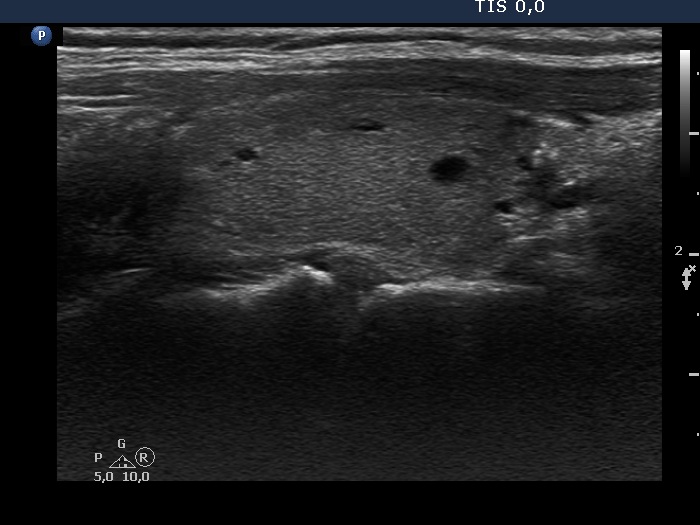

Second examination 9 months after surgery (second row of images):

Clinical presentation: The patient had no complaints.

Palpation: no abnormality.

Ultrasonography: The right and the left lobe remained unchanged except for the appearance of a moderately hypoechogenic lesion in the lower, isthmic part of the right lobe. This lesion contained various hyperechogenic granules and was avascular on Doppler mode. The ultrasound presentation stood for a granulation around surgical thread.

The lesion which has appeared on post operative ultrasound might be a regenerative tissue or a granulation around surgical thread. The latter is more likely because the former usually disappears within 4 months after the operation.